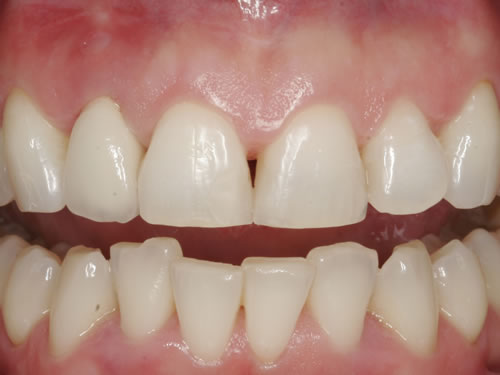

Eine besondere Herausforderung ist die Oberkieferfrontzahnregion. Der Wunsch nach einem perfekten Resultat ist geradezu selbstverständlich. Jeder möchte große, weiße Zähne und ein gesundes, reizloses Zahnfleisch besitzen (Abb. 3.30).

Abb. 3.30: Perfektes Resultat einer Versorgung.

Häufig führt ein Zahnverlust zu einem Verlust von Knochen (Hartgewebe) und der bedeckenden Schleimhaut (Weichgewebe). Besonders im sichtbaren ästhetisch sensiblen Bereich ist es aber notwendig, dass sowohl Hart- als auch Weichgewebe so wiederhergestellt wird, dass im Idealfall das Zahnimplantat mit seiner Krone dem Aussehen des ehemaligen gesunden Zahn entspricht. Als Erfolgskriterien werden aus zahntechnischer Sicht die Form, Farbe und Größe der individuellen Krone angesehen. Aus medizinischer Sicht gibt es wichtige Erfolgskriterien, die die Implantatposition, die Implantatlänge, den Implantatdurchmesser, den Zahnfleischrand im Vergleich zum Nachbarzahn und die Zahnfleischpapillen zwischen den Zähnen beinhalten. Zusätzlich braucht man ein zahntechnisches Labor, das mit der Keramikverarbeitung ein natürliches Aussehen gestalten kann. Nur, wenn alle Parameter perfekt sind, ist das Ergebnis perfekt. Das macht den Einzelzahnersatz im Oberkieferfrontzahngebiet zu einer echten Herausforderung.

Nach der Entfernung von Zähnen kommt es schnell zu Knochenverlust (Resorptionen) und entsprechendem Verlust von Schleimhaut. Die Schleimhaut kann durch bestimmte Operationstechniken wiederhergestellt werden, in dem man freie oder gestielte Bindegewebstransplantate z. B. vom Gaumen entnimmt und das fehlende Material so ersetzt. Das Weichgewebe kann in unterschiedlichen Behandlungsphasen korrigiert werden. In vielen Fällen wird es während der Implantation oder bei der Freilegung verbessert. Manchmal müssen Feinkorrekturen auch nach Eingliederung der fertig gestellten Krone erfolgen, wenn ästhetische Einbußen vorliegen. Häufig hat die Zahnfleischkorrektur auch noch einmal die Änderung der endgültigen Krone zur Folge (Abb. 7.14, 7.15).